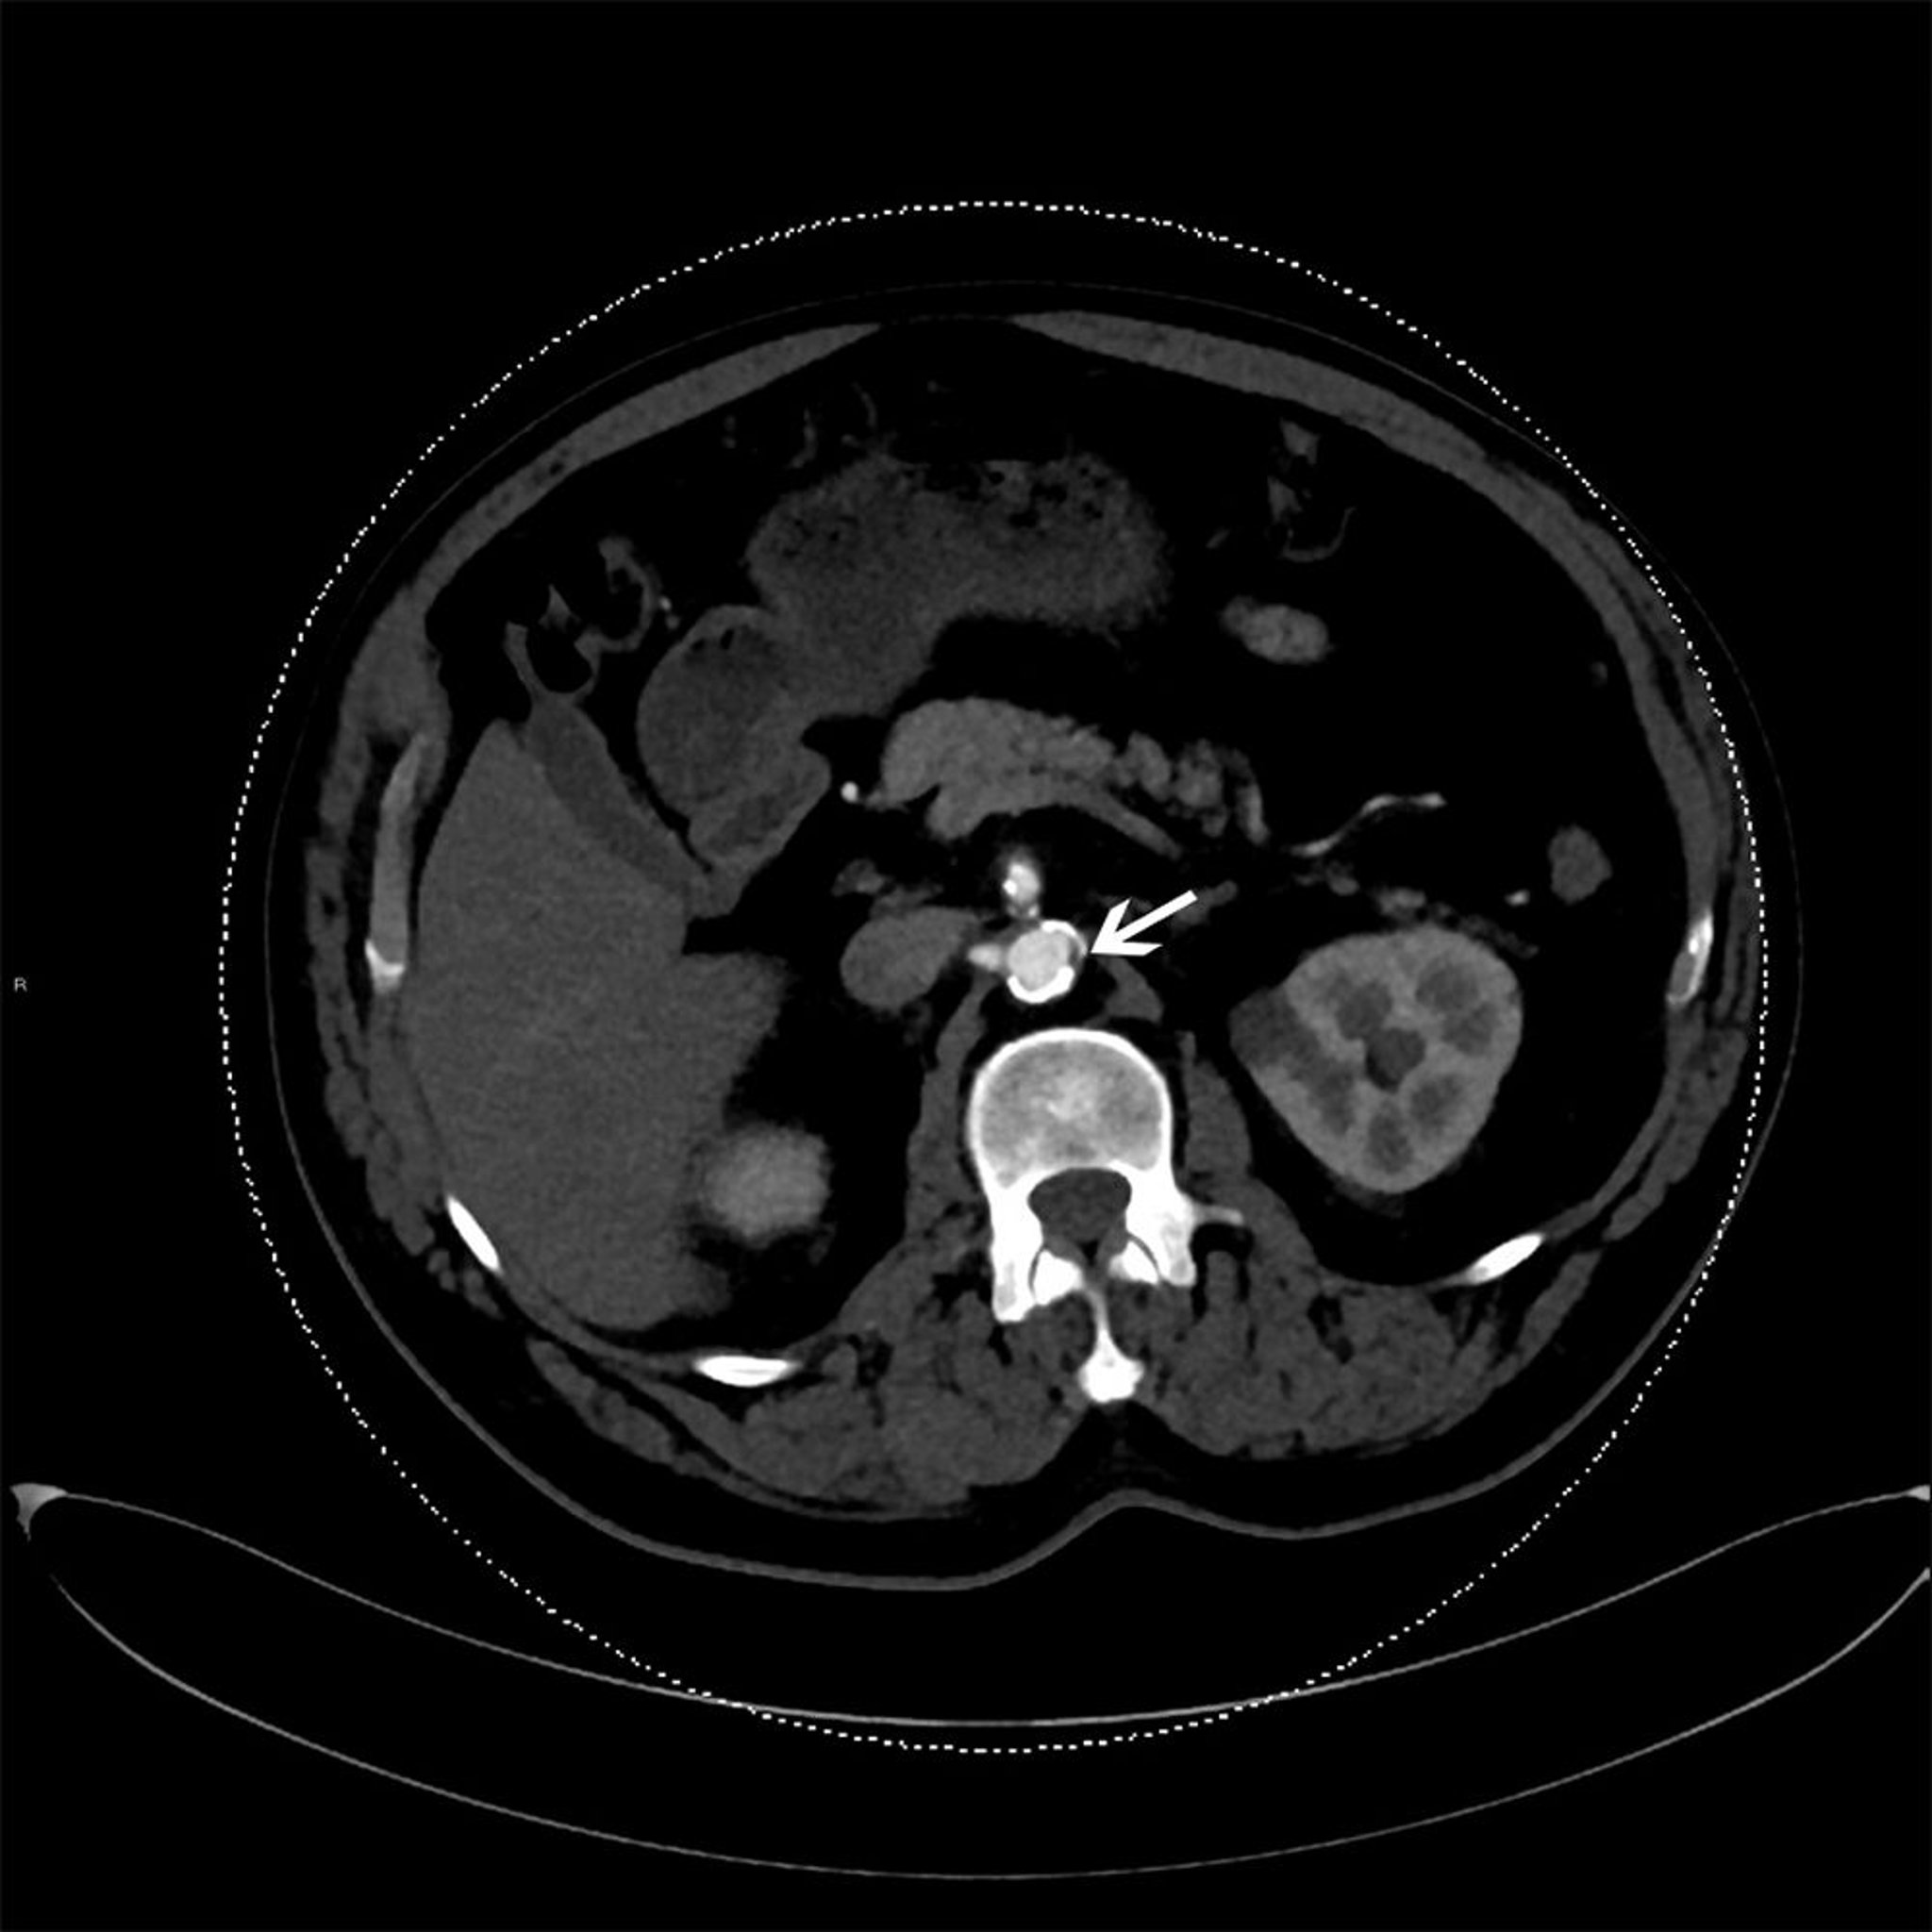

プラークの形態および特徴を評価できる非侵襲的な画像検査として以下のものがある:

• CT血管造影:冠動脈の有意な病変を同定する目的で臨床的に用いられる

免疫シンチグラフィーは,脆弱なプラークに集積する放射性トレーサーを使用する非侵襲的な代替検査法である。血管構造のPET検査は,脆弱なプラークを評価するための新たなアプローチである。

全てのアテローム性プラークに同様のリスクがあるわけではないことから,特に破綻しやすいプラークを同定する方法として様々な画像技術(例,PET)が研究されているが,いずれも臨床導入には至っていない。

アテローム性動脈硬化の危険因子があるものの,虚血の症候がみられない患者では,脂質プロファイル以外の追加検査の役割は不明である。内膜内側厚を測定するための頸動脈超音波検査やアテローム性プラークを検出できる他の検査法など,複数の画像検査法が研究されているが,それらは危険因子の評価や確立された予測ツールを上回るほどには虚血イベントの予測を改善できておらず,推奨されていない。ただし冠動脈カルシウムに対する(すなわちカルシウムスコアを得るために行うための)CT撮影は例外で,これについてはリスクの再分類に関してより頑健なエビデンスが得られており,リスク推定の精緻化および特定の患者(例,中程度のリスクを有する患者,若年での心血管疾患の家族歴がある患者)に対するスタチン療法の判断に有用となる可能性がある。